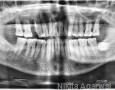

Pictures

Baseline